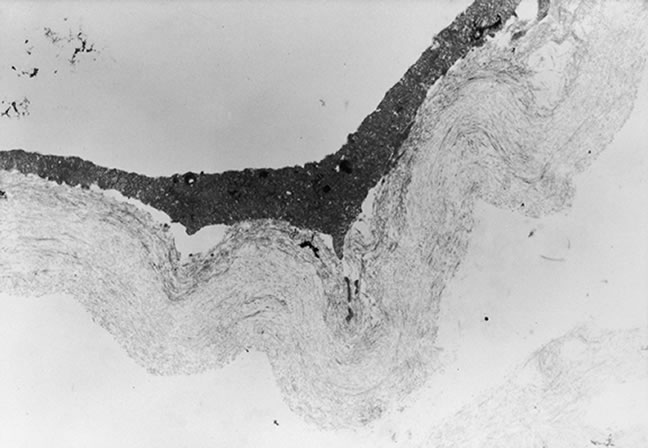

A different mechanism is required to explain the development of vitreous cortical shrinkage that occurs in the region of the vitreous base following vitrectomy. The ability of fibroblastic cells of different proliferative potential to contract a collagen latticework was first described by investigators evaluating the wound healing response in skin.40 Subsequent investigations in the dermatologic and ophthalmologic literature corroborated the applicability of this system for the testing of antiproliferative and anticontractile drugs.41,42 Clinical investigators pointed out the applicability of this experimental system as an explanation for contraction of the vitreous gel by dispersed intraocular cells.43,44 A variety of ocular cell types including dermal, scleral, or chorioretinal fibroblasts; pigment epithelial cells; and glial cells, in decreasing order of magnitude, will contract a clear gel of type I or type II collagen to a small fraction of its original volume with resultant opacification. Scanning and transmission electron micrographs of contracted gels reveal similarities with specimens of contracted vitreous taken from experimental animals and humans with PVR (Fig. 5). This process, termed hypocellular gel contraction, requires the presence of either serum, specific serum components, or other non-serum-derived growth factors to occur. Thrombin, transforming growth factor-β, platelet-derived growth factor, and fibronectin have all been shown to stimulate this process and can substitute for the serum requirement to variable degrees.45,46 Similarly, other pharmacologic compounds, which either intrinsically inhibit cellular contractility47–50 or interfere with cellular attachment to collagen through fibronectin-mediated binding sites51,52 can inhibit this process. Conventional and low molecular weight heparin also inhibit cellular attachment to collagen and, consequently, contraction. Various heparin forms also inhibit collagen polymerization.52,53 Antiproliferative compounds that innately inhibit the cellular contractility process include steroids, certain fluoropyrimidines, colchicine, and paclitaxel (Taxol).53

Histologic and ultrastructural studies of contracted gels disclose consistent morphologic changes that account for these contractile events. Pigment epithelial cells cultured on plastic demonstrate a rounded or cuboidal morphology when subconfluent. It has been previously shown that when pigment epithelial cells are cultured on either vitreous, collagen, or fibrin they assume a more mesenchymal configuration, including the development of dendritic extensions and lamellipodia.56 It is believed that the development of these lamellipodia are critical for locomotion of cells and for the generation of the tractional forces. Histologic cross sections of contracted gels reveal that the cells may produce profound volumetric changes in gels without the development of typical cellular membranes. In contracted gels, cells appear to be dispersed at uniform distances with relatively infrequent cell interactions, particularly in the case of fibroblasts (Fig. 7). It is believed that the mechanism of contraction in these cases relates to compaction of vitreous fibrils adjacent to cells through membranous interactions between fibronectin and collagen binding sites on the cells and individual collagen fibrils and HA with resultant extrusion of water.

Fig. 7. A low-power cross section of experimental gel contracted by dermal fibroblast. Note the sparse spacing of cells and lack of development of syncytial contractile membrane. Cells assume spindle morphology and occasionally demonstrate cell interactions through lamellipodia. (× 120).